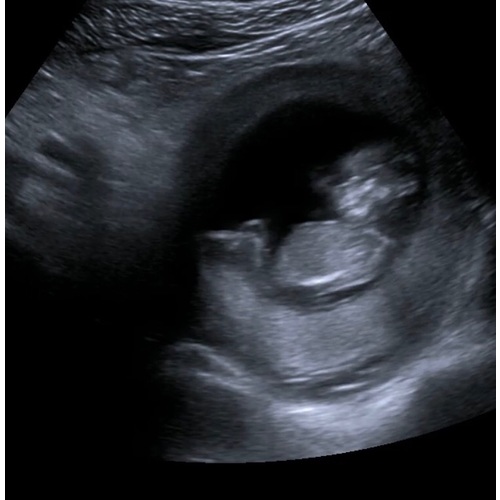

Hier 11 weken en 5 dagen.. Wat denken jullie? 😍